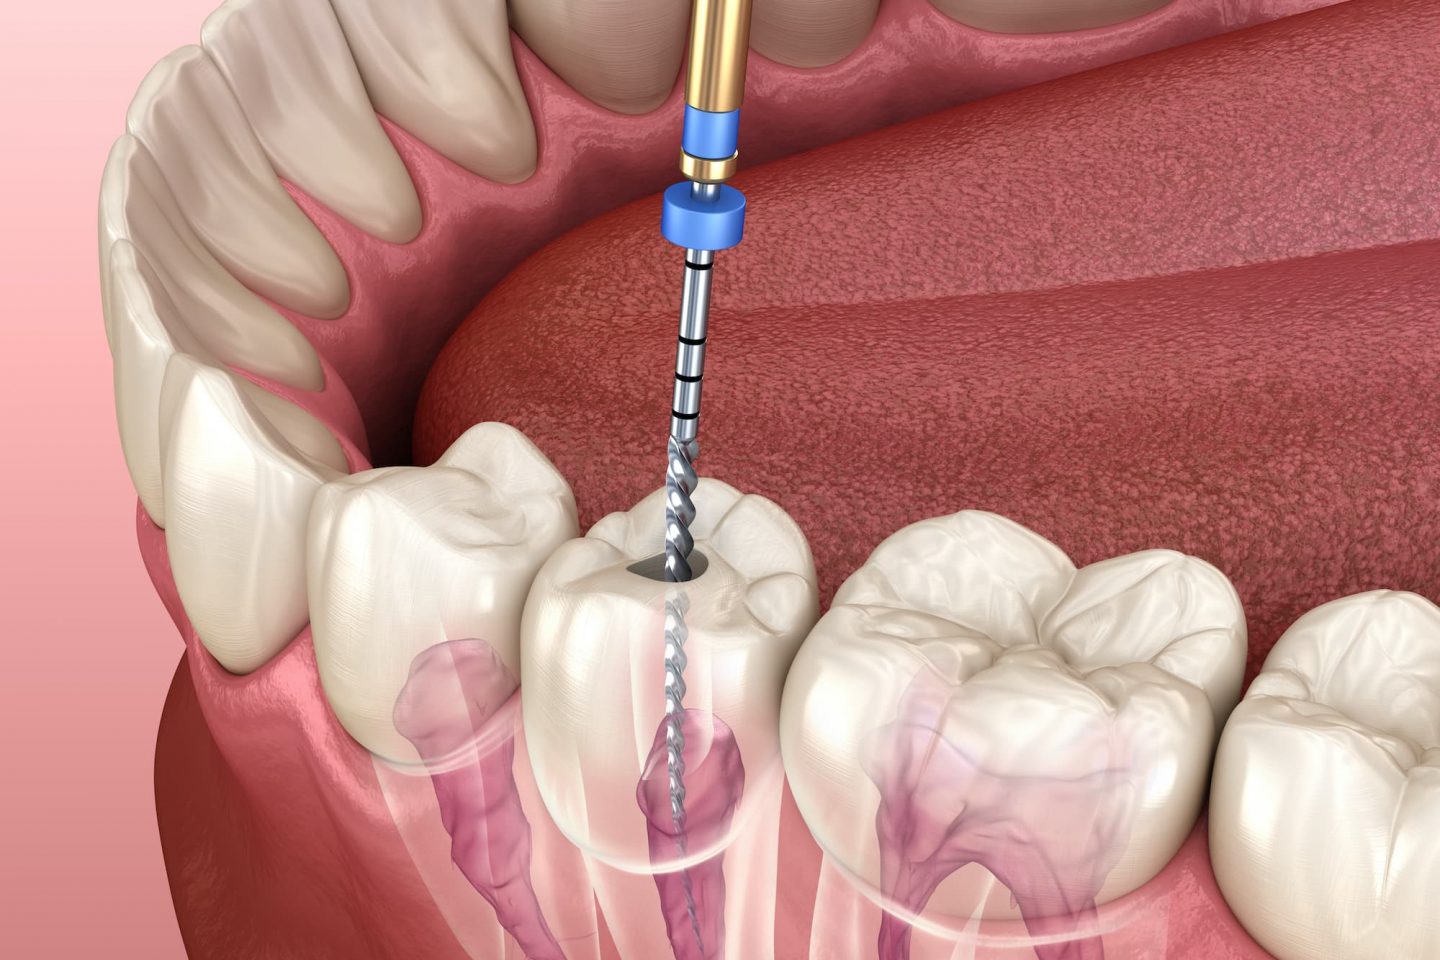

Root Canal Treatment

Pain-relieving treatment to save infected or damaged teeth.

Periapical / Endodontic Surgery

Surgical treatment for infections around tooth roots.